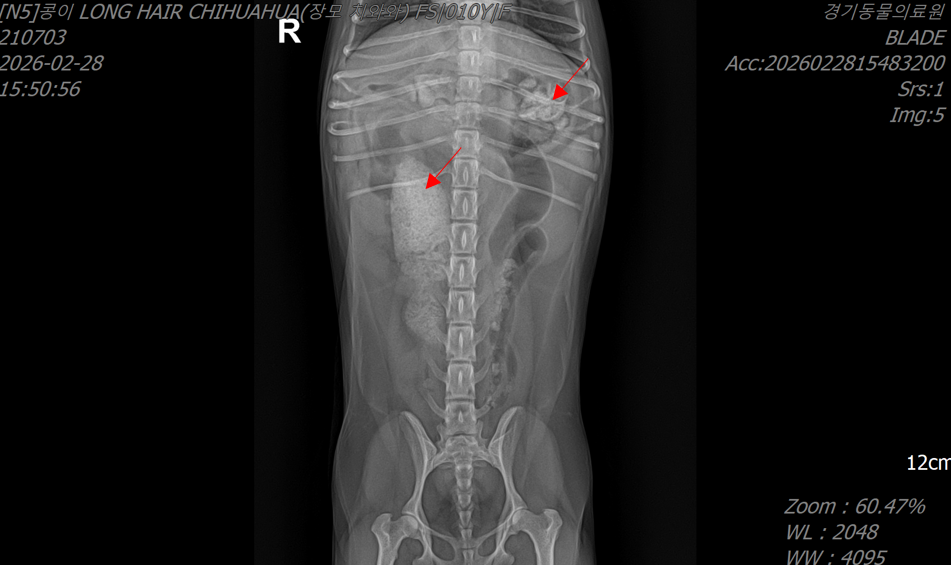

- 방사선 검사에서는 위와 소장 부위에 뼈로 의심되는 이물이 관찰되었으며,

방사선 검사: 위와 회장 부위에 뼈로 의심되는 이물 확인

<방사선 검사>